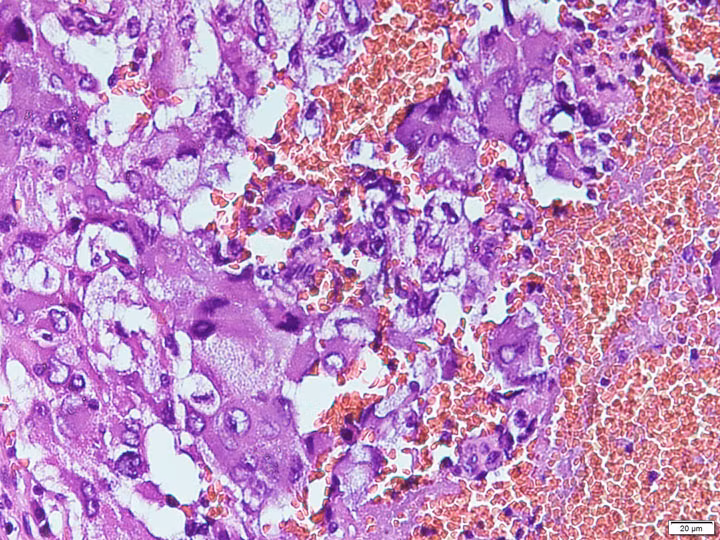

![]() |

| Hình ảnh U tế bào ưa chrom hỗn hợp dưới kính hiển vi - Ảnh BVCC |

Theo BSCKI. Phạm Thị Hoa, Khoa Giải Phẫu bệnh cho biết: U tế bào ưa chrom hỗn hợp xuất phát từ các tế bào ưa chrom của tuyến tủy thượng thận. Đây là u ác tính hiếm gặp chỉ ghi nhận vài ca bệnh trong y văn và rất khó phát hiện.

Để xác định chính xác thể U tế bào ưa chrom hỗn hợp chỉ có thể tiến hành xét nghiệm mô bệnh học. Đây là tiêu chuẩn vàng để xác định chính xác thể bệnh và giai đoạn bệnh từ đó giúp các bác sĩ lâm sàng đưa ra hướng điều trị tốt nhất cho người bệnh.